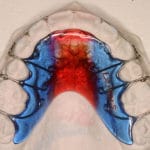

Pour les enfants et les jeunes plutôt des appareils amovibles, ainsi que des appareils fixes collés (pièces métalliques) pour aligner les dents. Ceux-ci peuvent être choisis en option transparentes.